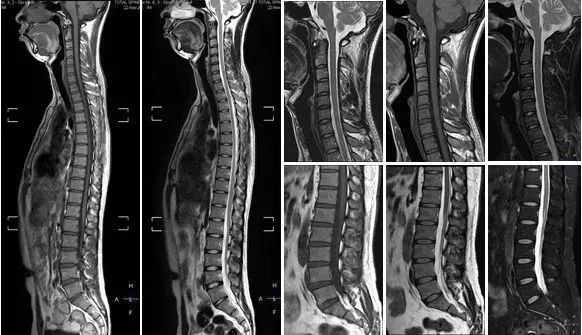

磁共振成像(MRI)

辐射:无

磁共振成像(MRI)有时也被称作“核磁共振”,它没有“核”,更没有辐射!!!

它的显影原理,就是将身体里的水分子“摇一摇”振动,然后再平静下来,以此来探测水分子的变化。水多的地方就是磁共振成像信号最强的地方,大脑、脊髓、椎间盘、关节软骨是磁共振最爱的部位。